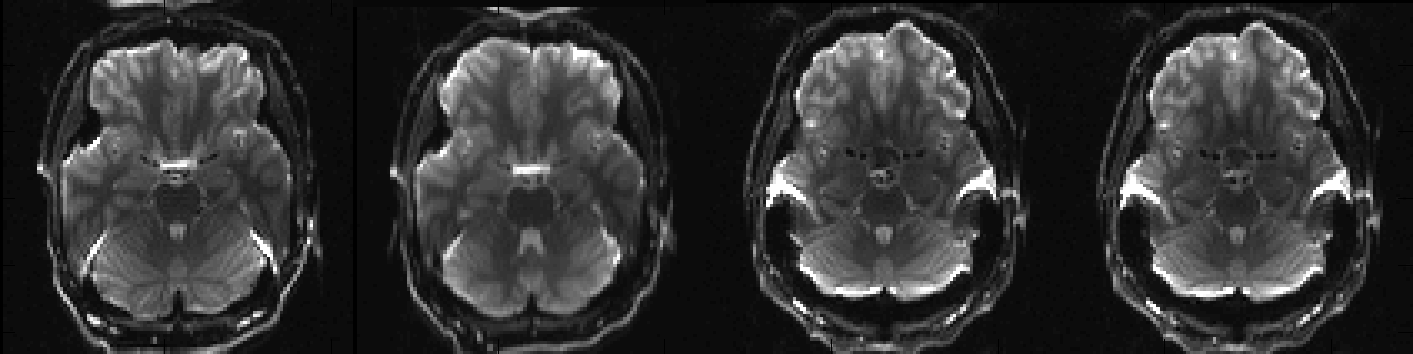

Above you can see a selected slice from the four volumes in an example file called my_b0_images.nii.gz. It is immediately obvious that the distortions in the first two images are vastly different from those in the two last images. If we take a look at the associated acqparams.txt file

we can see why. The two first images have been acquired with negative phase-encode blips in the y-direction, which means that signal from an area with "higher than expected" field (such as just above the ear-canals) will be displaced downwards. Conversely the two last images have been acquired with positive blips which means that signal from those same areas would be displaced upwards.

In addition to that we can see that the second image looks a little bit different to the first, despite having been acquired with identical parameters. This may mean that the subject moved between the acquisitions of the two images.